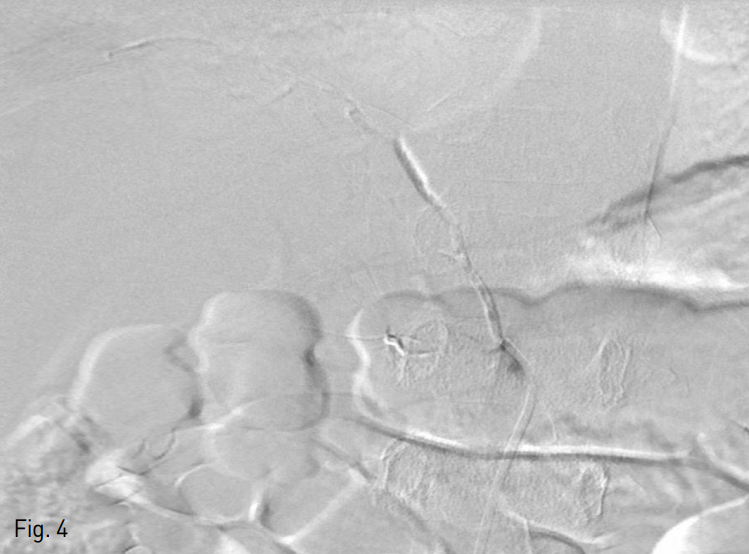

이후 4Fr cobra catheter를 통한 추적 오른쪽 아래가로막동맥조영술에서 상, 중 부신동맥에 대한 색전은 잘 확인되나, 하 부신동맥을 통한 혈류 흐름이 확인되었다 (Fig. 3A). 이에 하 부신동맥에 대한 보다 자세한 평가를 위해 microcatheter를 사용하여 하 부신동맥을 초 선택하였고, 선택적 조영술 상에서 오른쪽 부신의 하부 실질이 확인되나, 활동성 출혈이 있는지 여부는 확실히 배제할 수 없었다. 이에 Gelfoam (Alicon, Zhejiang, China)을 이용하여 색전을 시행하였다. 그러나 시술 과정 중 작은 가성동맥류가 확인되어 (Fig. 3B), NBCA와 Lipiodol 혼합물을 사용하여 추가 색전술을 시행하였다. 이후 추적 오른쪽 아래가로막동맥조영술에서 혈관 외 유출이 없음을 확인하고 시술을 종료하였다 (Fig. 4).

Fig. 4

After embolization, the extravasation of contrast medium no more was deteted.